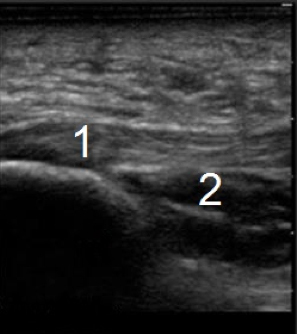

Foot & Ankle Plantar Fasciitis Image

Plantar Fascia

Inferior Margin